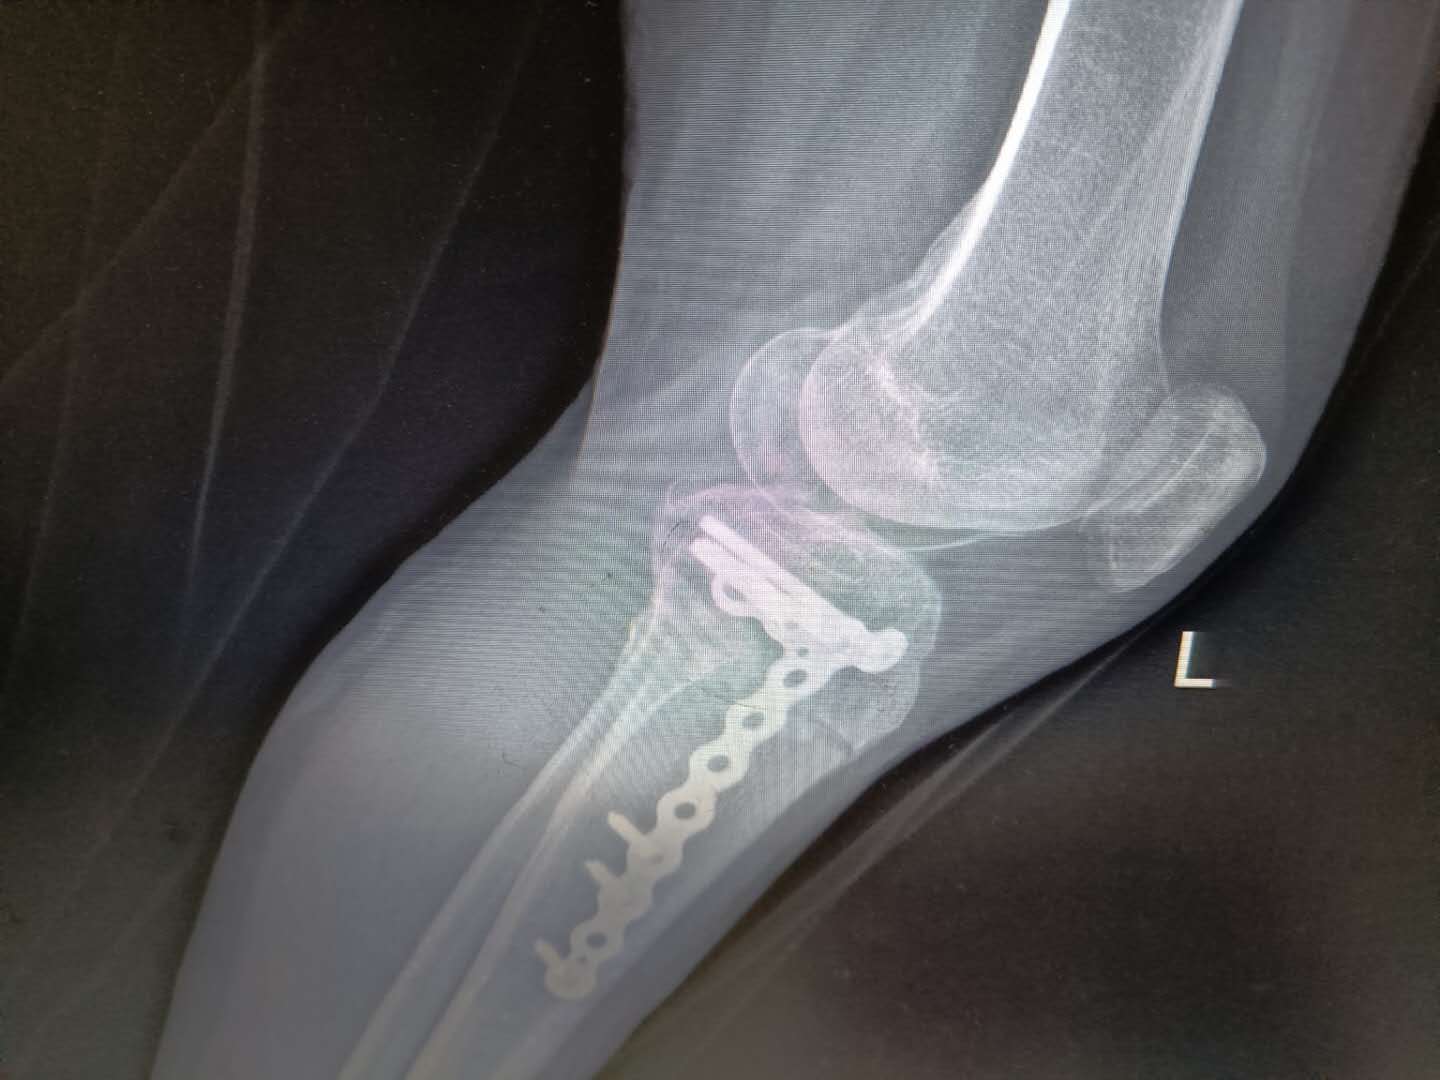

为确保万无一失,经专家组充分研究讨论后,决定手术由刘卓华、刘文志为首的专家团队共同完成,并制定了详细周密的手术方案。一切准备就绪,专家团队成功为罗女士实施了左胫骨平台陈旧性骨折内翻畸形截骨矫形术+内侧副韧带紧缩术+石膏外固定术。

术中,截骨、垫高、植骨、复位、紧缩韧带、平衡膝关节软组织…一系列动作轻巧娴熟,经过2小时的紧密配合,膝关节稳定,恢复了下肢力线及平台的平整性,做到精准、高效,顺利打赢了“膝关节保卫战”。

(术后影像图)

成功的手术只是一个方面,术后的康复训练同样重要。髋股膝胫科制定了详细的康复计划,一步步地指导罗女士进行下肢肌肉训练。出院时,罗女士膝关节下肢力线恢复、疼痛缓解,膝关节功能恢复满意。